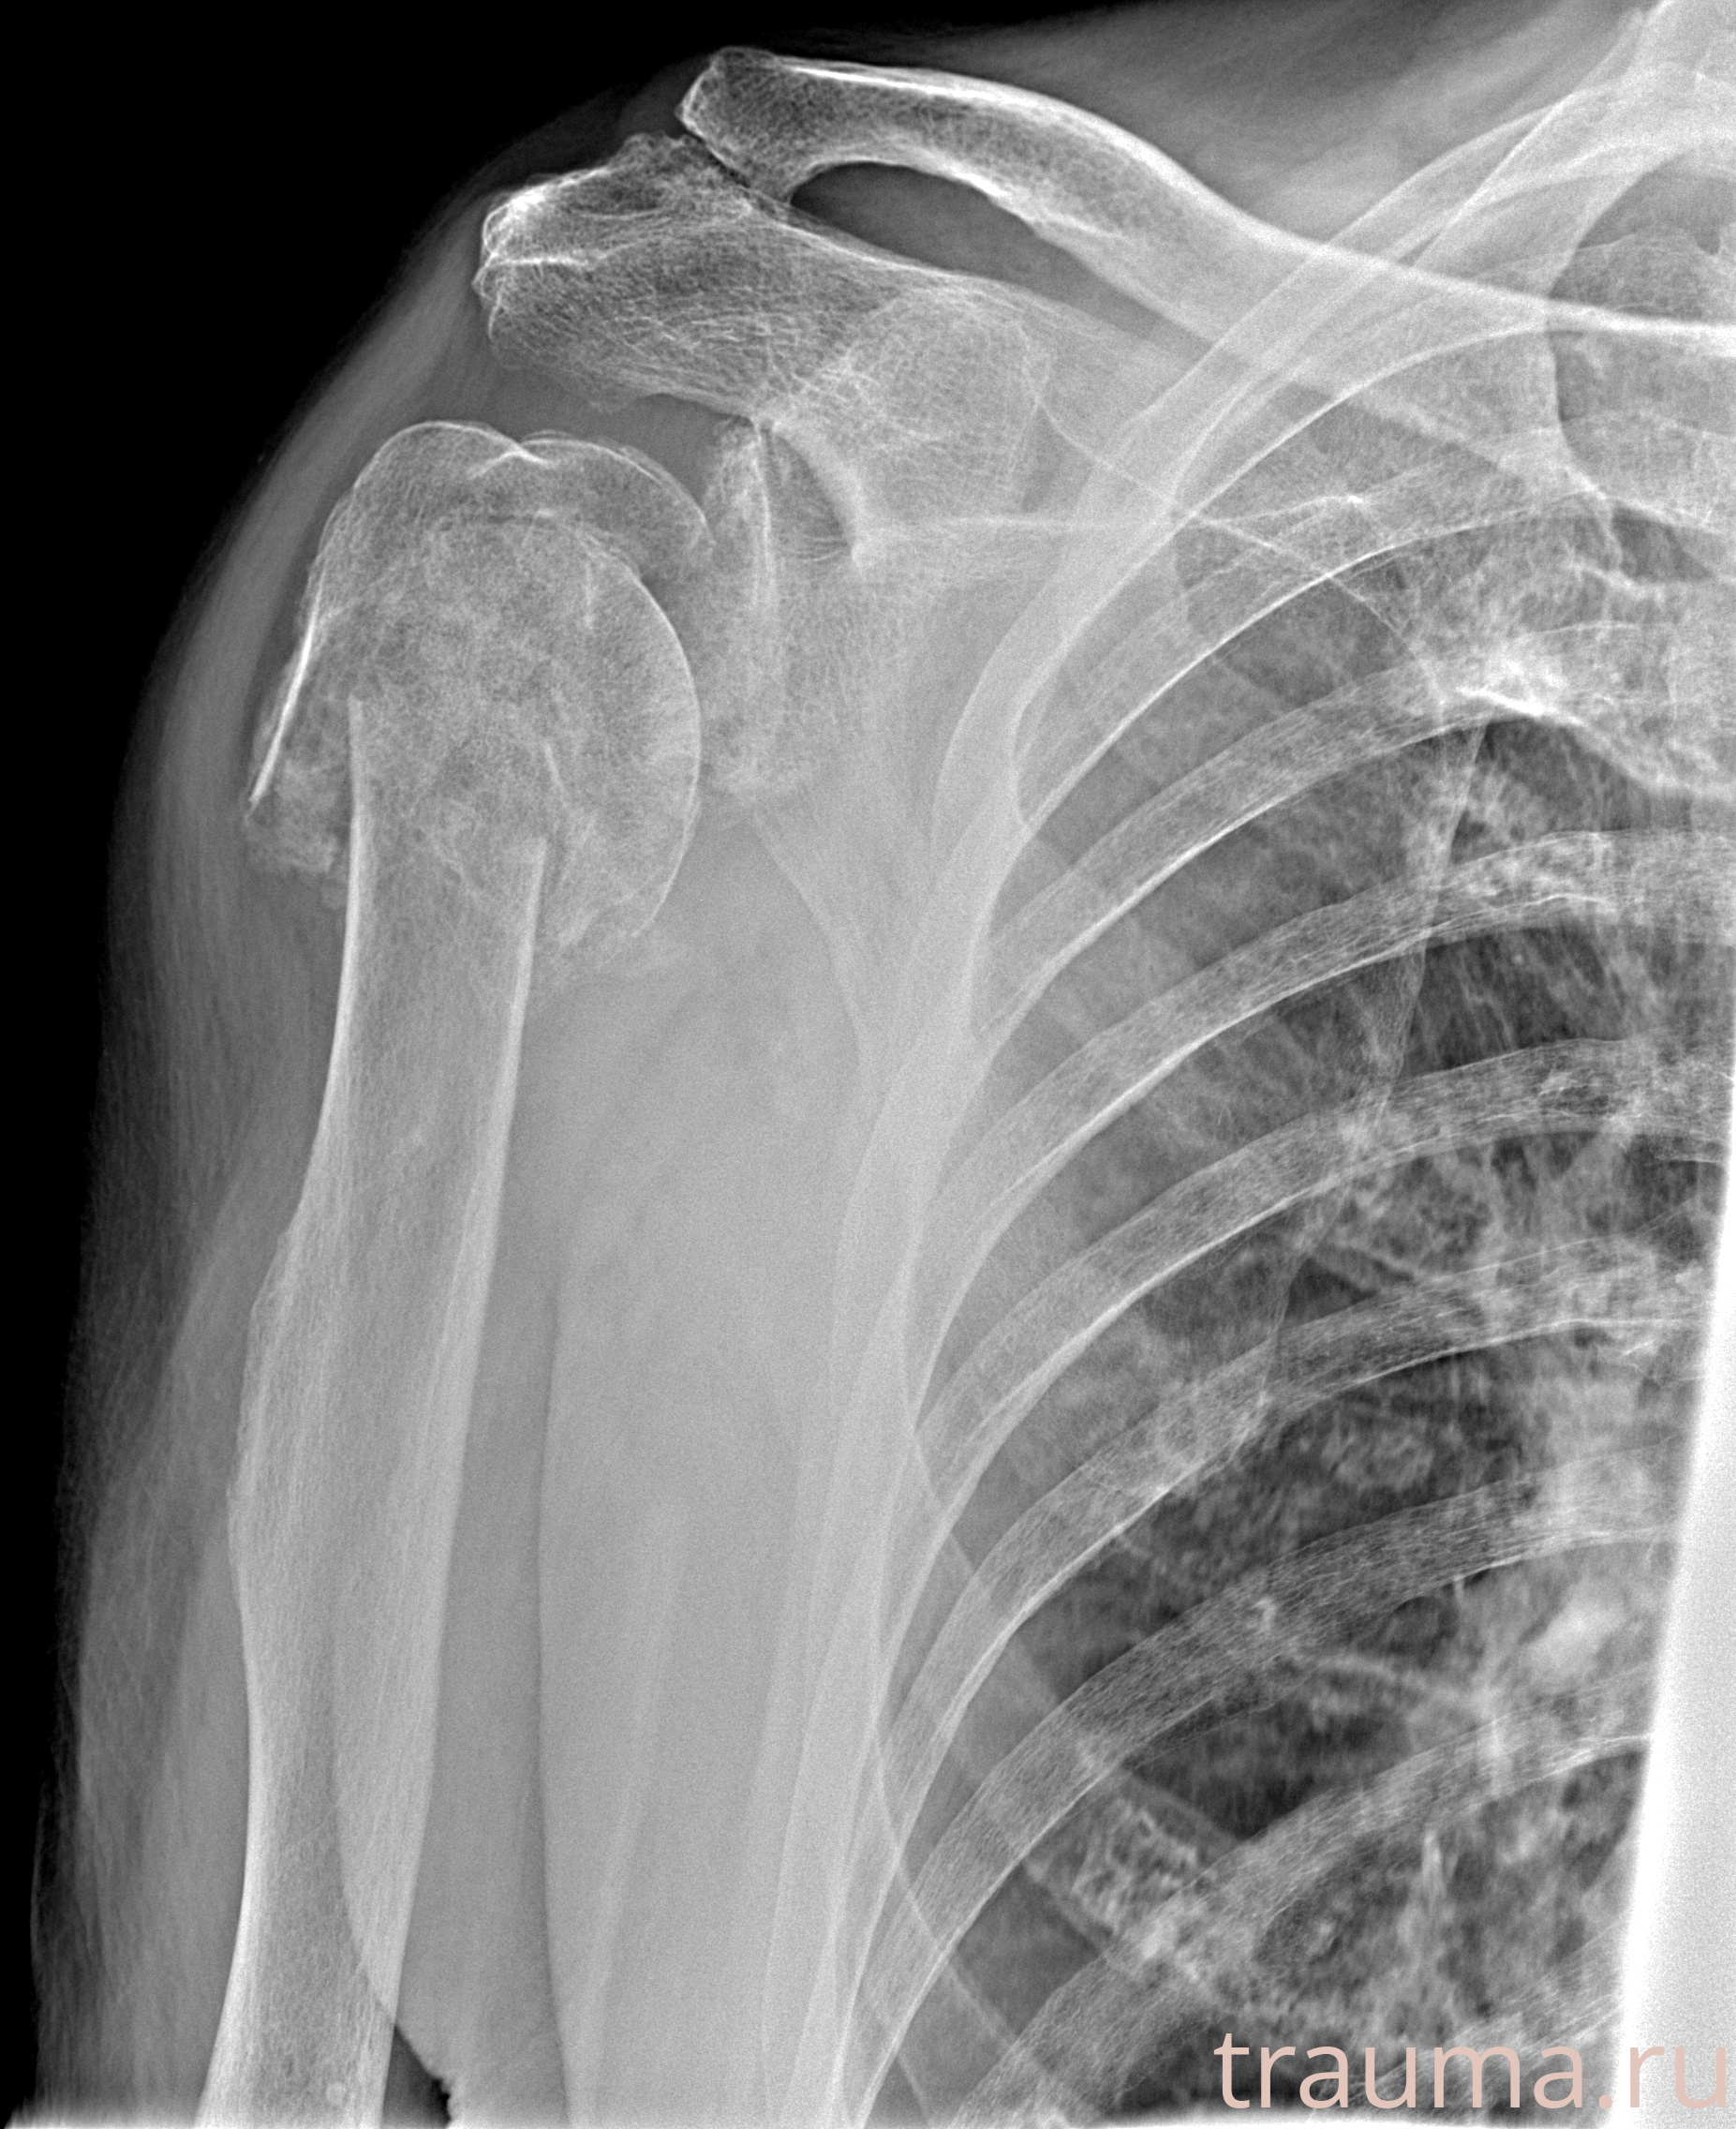

Рентгенограммы

Рентген на дому: по вашему адресу приезжает врач-рентгенолог, травматолог-ортопед с мобильным рентгеновским аппаратом, проводит диагностику травмы или заболевания, делает необходимые рентгенограммы, дает рекомендации по дальнейшему лечению. Получить качественные снимки в домашних условиях возможно благодаря уникальной методике, разработанной МосРентген Центром для института  Склифосовского